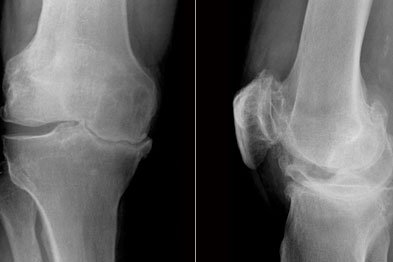

- الأشعة السينية: لتقييم حالة العظام واستبعاد الخشونة الشديدة أو التشوهات.

- الرنين المغناطيسي: الأداة الأهم لتحديد مكان القطع، نوعه، ودرجته، وهل هو مؤثر على وظيفة المفصل أم لا.

التشخيص الصحيح هو حجر الأساس لاختيار أنسب طرق علاج غضروف الركبة.